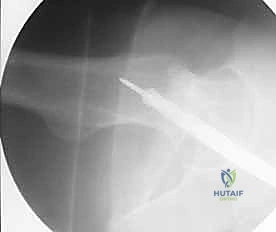

باستخدام جهاز الأشعة السينية المرئي (C-arm Fluoroscopy)، يقوم د. هطيف برد الكسر (إعادته إلى مكانه الطبيعي) عن طريق الشد والدوران من الخارج، دون الحاجة لفتح العظم.

يتم عمل شق جراحي صغير (حوالي 3-5 سم) في منطقة الورك أعلى المدور الكبير (Greater Trochanter) أو الحفرة الكمثرية (Piriformis Fossa). يتم إدخال سلك توجيهي (Guide Wire) بدقة متناهية تحت جهاز الأشعة.